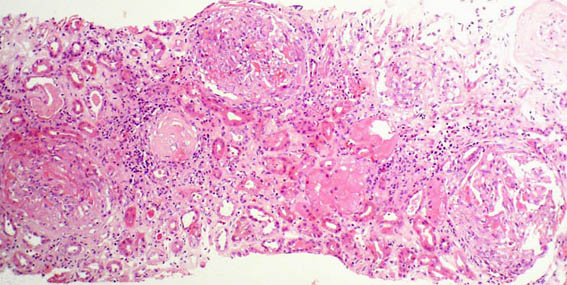

Figura 1. H&E, X100.